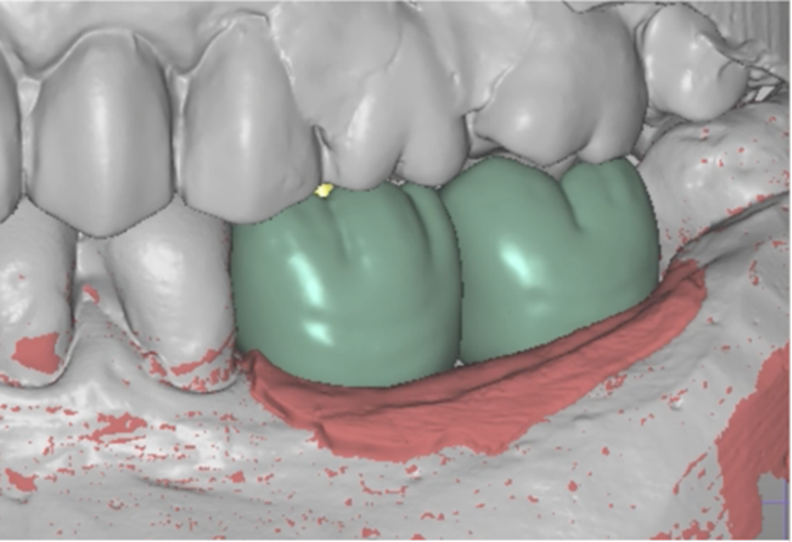

Selecionamos um caso clínico para ilustrar o fluxo de trabalho digital para Mini Cônico, onde foram planejadas duas coroas unidas nos elementos dentários 36 e 37 em zircônia monolítica, feitas sobre o pilar para próteses múltiplas.

Após o período de osseointegração dos implantes, a altura correta do transmucoso de cada Mini Cônico foi selecionada utilizando-se o medidor tunel check, e os pilares foram instalados com um torque de 20 Ncm. Sobre os componentes, foram confeccionados provisórios para a personalização do perfil de emergência.

Na etapa de escaneamento foi selecionado o transferente digital do Mini Cônico e optamos por trabalhar no fluxo e biblioteca do software Exocad (onde é realizado o design da prótese), o qual tem toda a linha de componentes da Implacil De Bortoli e de seus análogos digitais.

Neste caso, a prótese múltipla foi desenhada sobre o Mini Cônico e as duas coroas foram fresadas unidas. Após a maquiagem final da zircônia monolítica, as coroas foram parafusadas sobre o Mini Cônico com um torque de 10 Ncm.

Podemos acompanhar o passo a passo das etapas, desde a seleção da altura do transmucoso do Mini Cônico até a instalação das coroas unidas no fluxo totalmente digital sem a utilização de componentes metálicos.